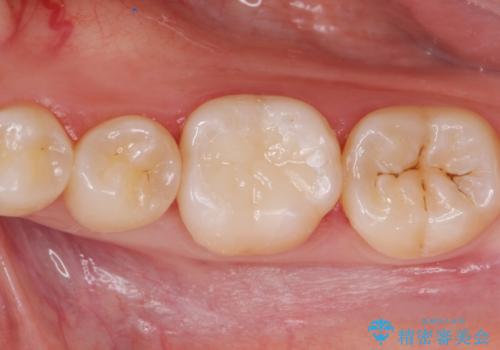

銀歯を白いセラミックに変えたい セラミックインレー